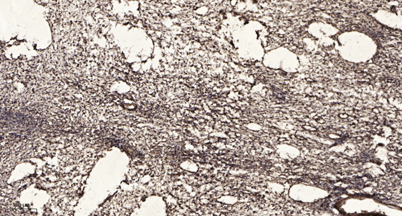

| Product name: | Sin3B rabbit pAb |

| Dilutions: | WB 1:500-2000;IHC-p 1:50-300; ELISA 2000-20000 |